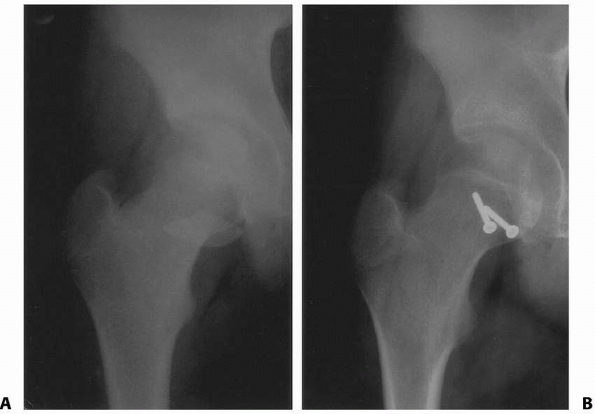

capsulotomy should be performed in order to decrease iatrogenic injury

to existing blood supply (Fig. 21-6A,B). It is

suspected that anterior capsulotomy does not damage the blood supply to

the femoral head as long as the intertrochanteric notch and the

superior lateral ascending cervical vessels are avoided.

| FIGURE 21-6 A,B. Percutaneous placement of a periosteal elevator along the anterior femoral neck should allow fenestration of the capsule while protecting the posterior and superior blood supply. |